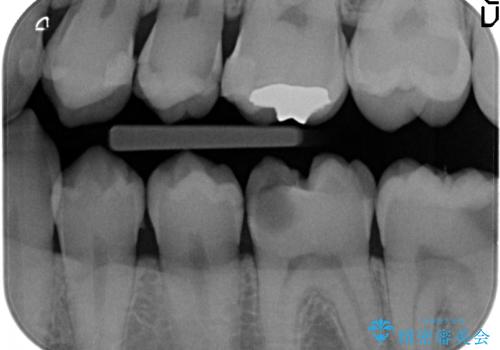

放置した虫歯の治療 親知らずの手前が虫歯

- 詰め物が取れて放置していたとのこと。

虫歯が大きかったため、被せ物(クラウン)としました。

親知らずを抜いてから治療しています。

幸い神経を取らずにすみました。